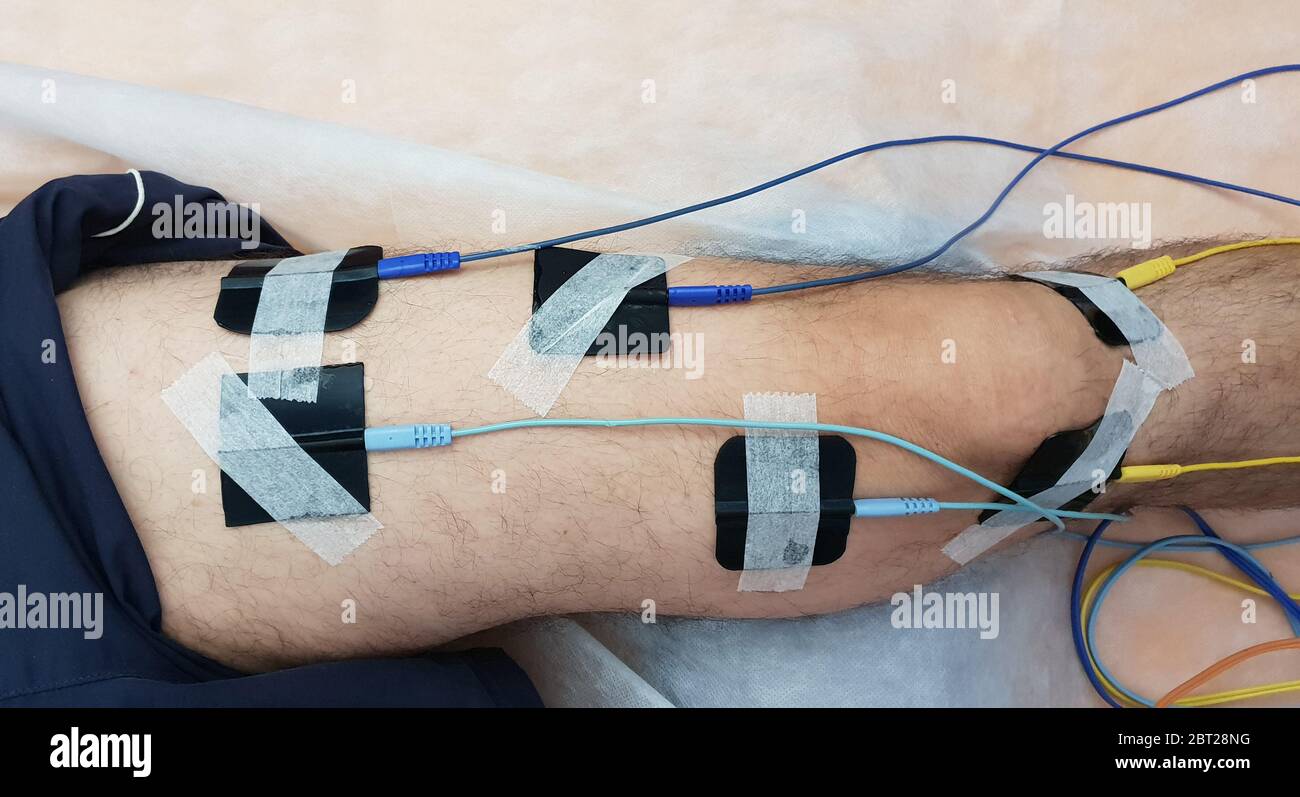

Électrostimulation des quadriceps comme thérapie de physiothérapie Banque D'Imageshttps://www.alamyimages.fr/image-license-details/?v=1https://www.alamyimages.fr/electrostimulation-des-quadriceps-comme-therapie-de-physiotherapie-image359009891.html

Électrostimulation des quadriceps comme thérapie de physiothérapie Banque D'Imageshttps://www.alamyimages.fr/image-license-details/?v=1https://www.alamyimages.fr/electrostimulation-des-quadriceps-comme-therapie-de-physiotherapie-image359009891.htmlRF2BT28NR–Électrostimulation des quadriceps comme thérapie de physiothérapie

Électrostimulation des quadriceps comme thérapie de physiothérapie Banque D'Imageshttps://www.alamyimages.fr/image-license-details/?v=1https://www.alamyimages.fr/electrostimulation-des-quadriceps-comme-therapie-de-physiotherapie-image359009884.html

Électrostimulation des quadriceps comme thérapie de physiothérapie Banque D'Imageshttps://www.alamyimages.fr/image-license-details/?v=1https://www.alamyimages.fr/electrostimulation-des-quadriceps-comme-therapie-de-physiotherapie-image359009884.htmlRF2BT28NG–Électrostimulation des quadriceps comme thérapie de physiothérapie